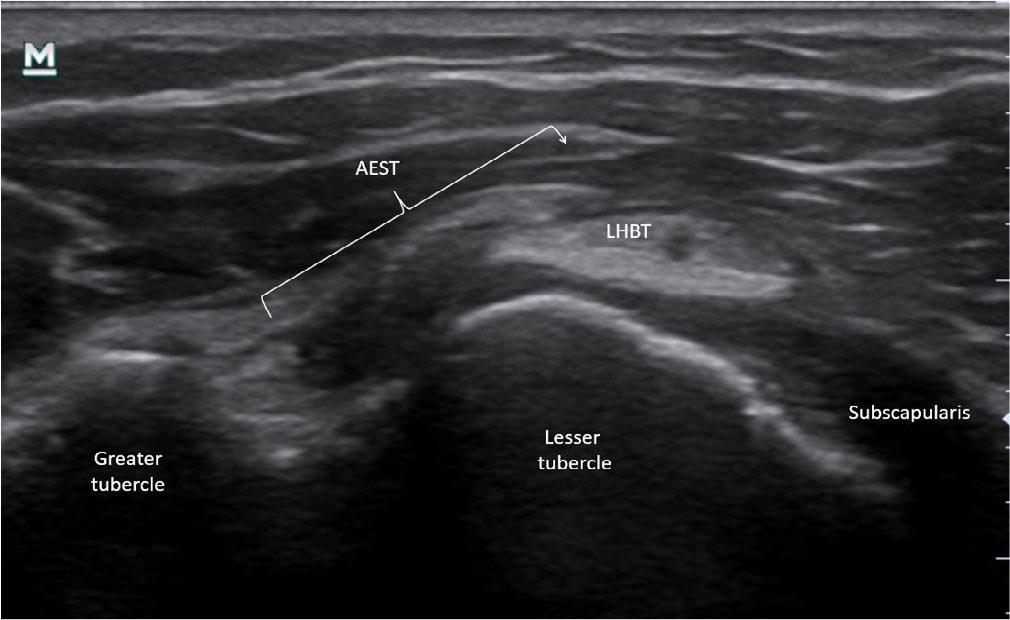

Aponeurotic expansion of the supraspinatus tendon (AEST) subluxation medial to the long head of the biceps tendon (LHBT) with a full-thickness supraspinatus tear in the right shoulder (case 7)

The most frequent abnormality was AEST dislocation with preserved intragroove LHBT, observed in six of 19 cases (31.6%) (Fig. 15). LHBT dislocation in the presence of intragroove AEST was identified in three cases (15.8%) (Fig. 16), while AEST intragroove subluxation with preserved LHBT alignment was found in another three cases (15.8%) (Fig. 17). Combined pathology included two cases (10.5%) of concomitant AEST and LHBT dislocation (Fig. 18), one case (5.3%) of LHBT subluxation with intragroove AEST, and one case (5.3%) of concomitant AEST and LHBT subluxation (Fig. 19). In four cases (21.1%), no abnormalities were observed.

Subluxation of AEST was identified in seven cases (36.8%) (Fig. 12 and Fig. 13). In two patients (cases 5 and 11), both the LHBT and AEST were dislocated over the lesser tubercle; in these situations, AEST at the rotator interval level was also classified as subluxated, as it extended beyond the anatomical boundaries of the interval. No cases of AEST dislocation within the rotator interval were observed.